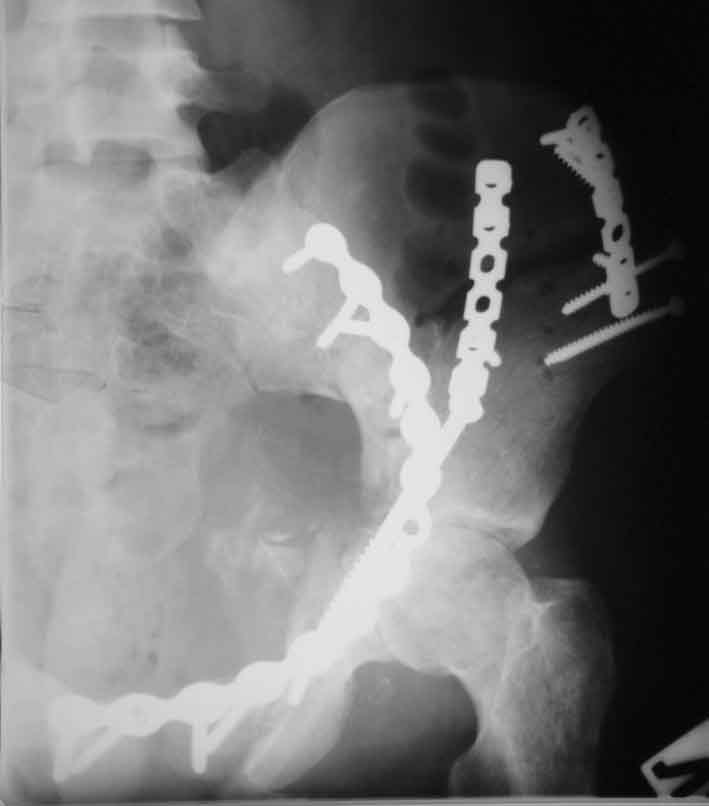

Рентгенограммы после операции

inlet

A>РО - картина не очень, есть видимость винтов во впадине

По всей видимости, вы имеете в виду канюлированный винт, который проецируется на вертлужной впадине. Та вот, он проведен не через лонную, а седалищную кость. Вертлужная впадина абсолютно интактна. Это хорошо видно на проекции inlet.